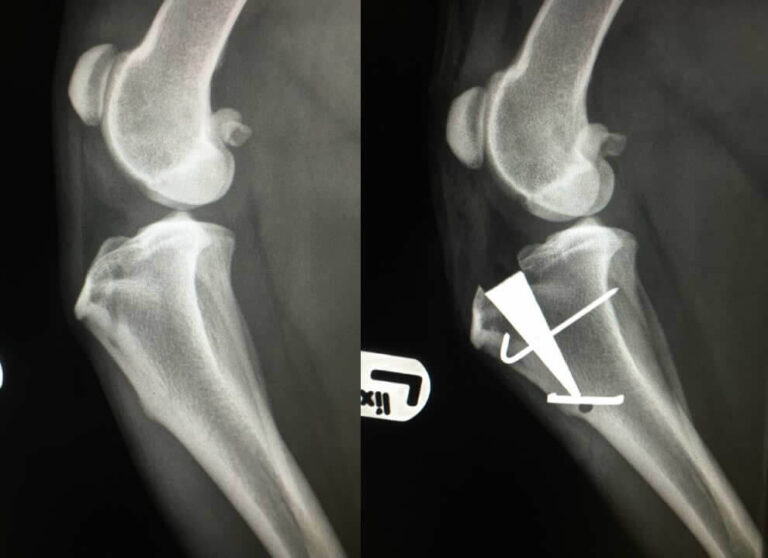

Xray images showing real fracture of broken leg bone under the knee Broken Knee Dog Humans have a similar anatomical structure to the dog's knee, but the ligaments are called the anterior and. How veterinarians diagnose torn knee ligament in dogs. A dog's broken leg may appear deformed or bent at an odd angle, especially if the pieces of a comminuted fracture have drifted out of their normal alignment. Our vet explains the different signs,. Broken Knee Dog.

Preoperative Xrays of a comminuted patella fracture (above). 3 months Broken Knee Dog In an open fracture, you might even see the end of the bone poking out of the open wound in the skin. Veterinarians diagnose a fully torn crcl by noting cranial drawer. If your canine companion has an accident and suffers a broken leg, a veterinarian will need to assess the severity and location of the. Humans have a similar. Broken Knee Dog.